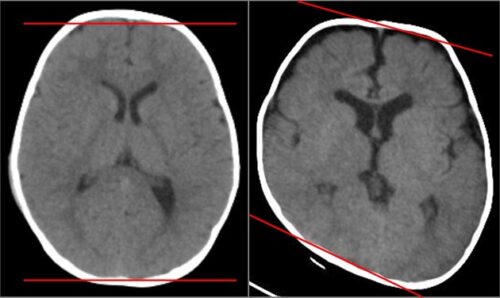

يعاني بعض الأطفال الرضّع من حالة تُعرف باسم تشوّه الرأس الموضعي أو “متلازمة الرأس المسطّح” (Plagiocephaly)، وهي حالة تُلاحظ عند وجود انبساط أو عدم توازن في شكل جمجمة الطفل، خصوصًا في الجهة الخلفية أو الجانبية من الرأس. هذا التشوّه يكون في العادة نتيجة الضغط المتكرر على جزء معين من الرأس خلال الشهور الأولى من عمر الطفل، وهي الفترة التي تكون فيها عظام الجمجمة لينة وقابلة للتشكّل بسهولة.

تشوّه الرأس الموضعي هو تغير في شكل رأس الطفل بسبب الضغط الخارجي المتكرر، مثل إبقاء الطفل لفترات طويلة في وضعية واحدة أثناء النوم أو الجلوس في مقعد السيارة.

يُعتبر شائعًا جدًا لدى الرضّع، وخاصة من ينامون دائمًا على ظهورهم دون تغيير الوضعية.